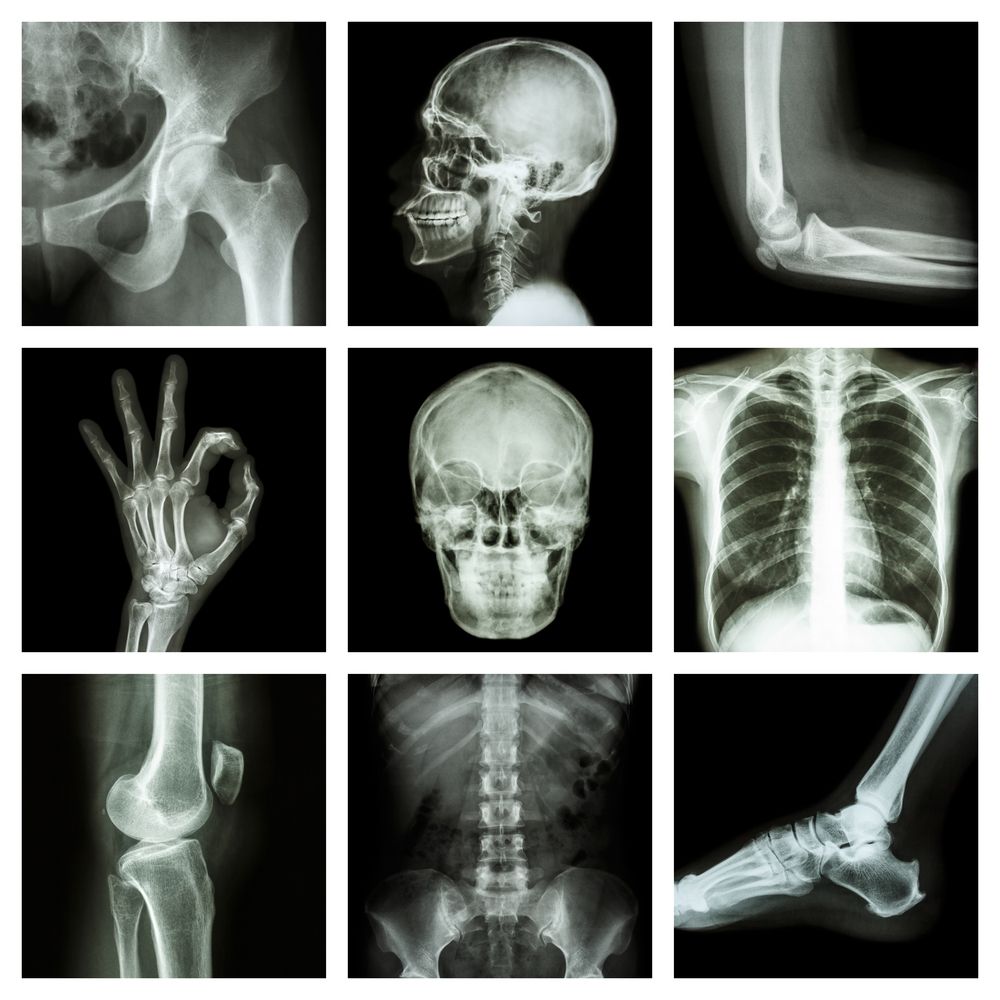

Non-enhanced CT scans for suspected renal colic often detect incidental findings.